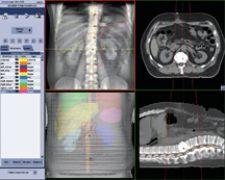

OBI integrated with Varian's VARiS Vision image and information management system and treatment planning software enables clinicians to pinpoint tumor location.

Varian Medical Systems On-Board Imager (OBI) accessory for the company’s Clinac and Trilogy linacs provides 3-D cone beam CT images that show anatomic changes while the patient is on the treatment table. By integrating OBI with Varian’s VARiS Vision image and information management system and Eclipse treatment planning software, clinicians can pinpoint tumor location and minimize radiation exposure to surrounding healthy tissue.